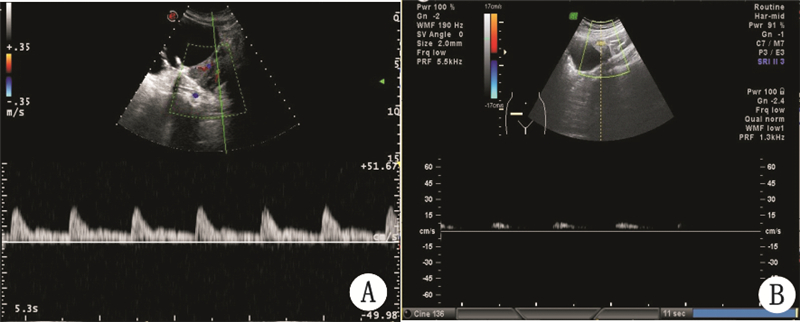

40例中不全扭转(即扭转小于360°)13例;完全扭转不伴坏死18例(扭转一圈以上);完全扭转伴卵巢坏死(扭转一圈以上,伴卵巢或输卵管坏死)9例。不同程度卵巢囊肿蒂扭转超声表现及患者情况见表 1。典型图例见图 1和图 2。

| A:完全扭转不伴坏死高阻动脉频谱;B:完全扭转伴坏死动脉频谱舒张期血流消失 图 2 卵巢扭转频谱图 |

妊娠时附件上升进入腹腔,宫底推开附件周围肠管,卵巢蒂部以其长轴为中心发生不同程度的扭转,较长的蒂部形成实性团块状组织,蒂部与卵巢一起形成大小不等的囊、实双块征。附件扭转时,蒂部血管受压,不全扭转或扭转程度较轻时,血流丰富,呈“麻花样”(图 1A),动、静脉频谱均可探及。完全扭转时因静脉回流完全被阻断,PW仅见高阻动脉频谱或舒张期血流消失(图 2A),静脉淤血,瘤体内高度充血,增大的瘤体刺激腹膜,引起急性下腹剧痛,探头触痛实验阳性;扭转程度重时间长时,仅见星点状血流(图 1B),PW为舒张期血流消失的动脉频谱(图 2B),或动静脉血流均消失,组织坏死,部分伴渗出液形成,与周围组织黏连,超声检查时发现瘤体边界不清,内部结构混乱,囊肿周围可见少量游离液体。因此二维超声可仔细寻找囊肿的蒂部和囊、实双块征及蒂部的探头触痛实验来诊断附件扭转的有无;彩色多普勒超声可以根据蒂部血流信号的有无及频谱的动静脉类型来判断扭转的程度[10]。